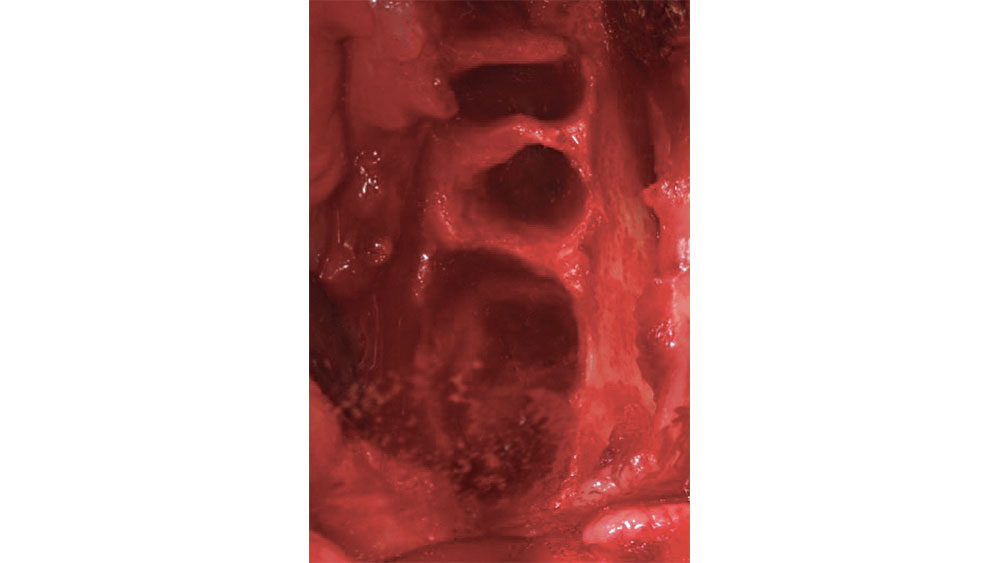

Figure 2: Five-walled extraction socket

Figure 2: Five-walled extraction socket (mesial, distal, buccal, lingual, apical).

In a five-walled socket, all the bony walls are present. Therefore, this type of extraction socket is the most predictable to treat. If the walls are thick (greater than 1.5 mm) and have the interseptal bone remaining, then grafting of the socket is not necessarily required (Fig. 2).